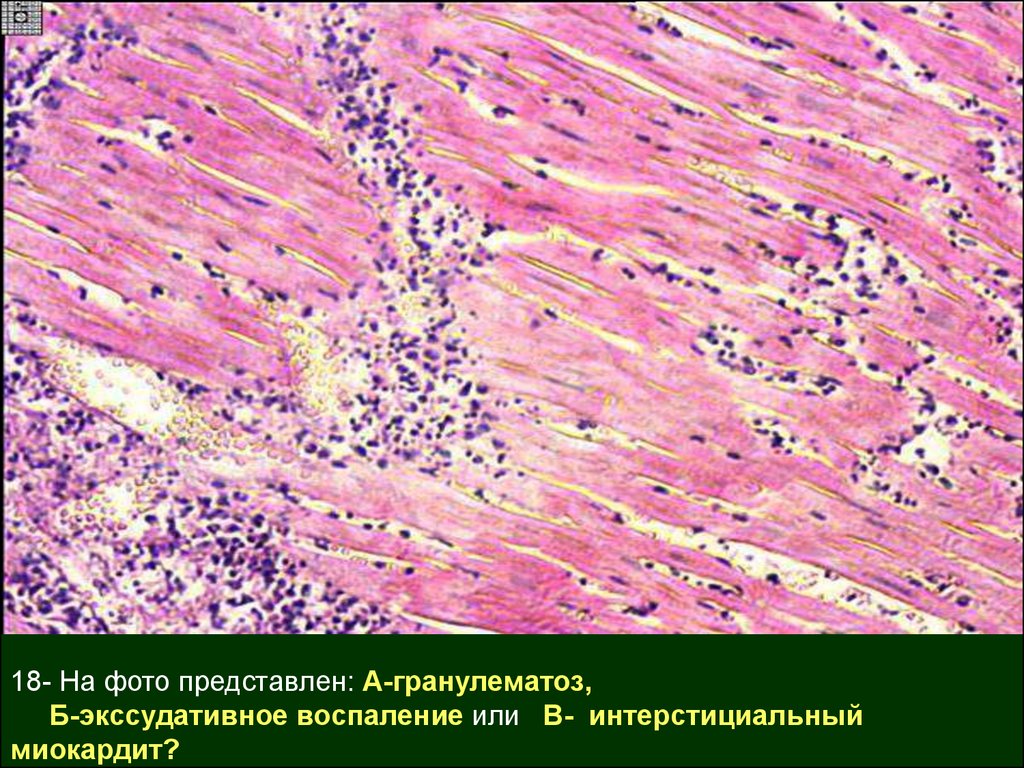

Межуточный миокардит: гистологические исследования

Раздел: Идеи и советы